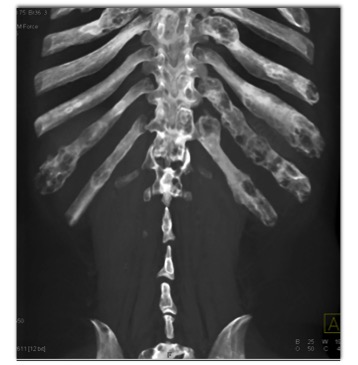

The best diagnosis in this case is?

multiple myeloma

fibrous dysplasia

metastatic renal cell carcinoma

Pagets Disease